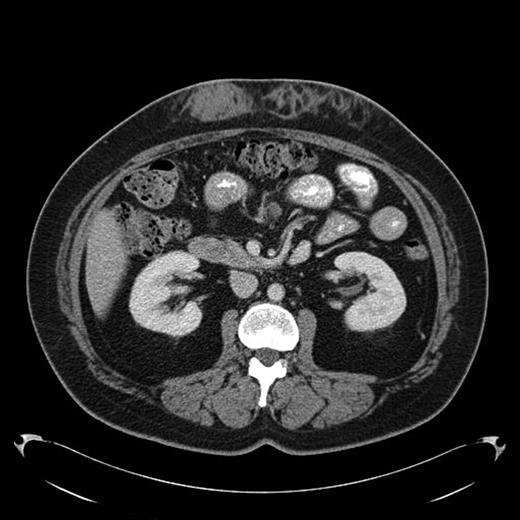

A 43-year-old female diagnosed with diabetes mellitus in 1986 after acute pancreatitis secondary to hypertriglyceridemia presented to our hospital in December of 2008 with a 2 year history of low grade fever of 99-100F. This was associated with chills and fatigue. Over the same time period she had noticed anterior abdominal wall nodularity, particularly at sites where she has been injecting her insulin. Her insulin requirement had also increased from a total of 60 units of NPH in a day to 170 units per day. Because of the subcutaneous nodularity at the site of injection a decision was made to switch the site of the insulin which resulted in lower blood glucose level and subsequently significant decrease in her insulin requirement to 120 units a day. This suggested poor absorption from the infiltrated site. At our clinic laboratory data showed normal white count of 5.4 × 10(9)/L with normal differential, normal hemoglobin of 12.9 g/dL with an ESR of 11 mm/hour, creatinine of 0.8 mg/dL and C-reactive protein of less than 3. As part of the work up for fever of unknown origin a CT-scan of the abdomen was obtained which showed infiltrative lesion in the anterior abdominal subcutaneous tissue with few calcifications Fig 1 & 2. Biopsy of the anterior abdominal wall nodular infiltrate was performed. Tissue cultures came out negative for infection. The biopsy showed eosinophilic material positive with Congo red staining and showing apple green birefringence when viewed under polarized light. Immunohistochemical staining showed this to be negative for AA, AL, or TTR amyloidosis. Liquid chromatography tandem mass spectrometry (LC MS/MS) detected peptides representing apolipoprotein E, apolipoprotein A-IV, SAP and Insulin. The amyloid deposits stained positive with anti-insulin. The presence of peptides from insulin and immunohistochemical reactivity with an anti-insulin antibody indicated that the amyloid deposits were caused by insulin injection at this site. Work up for systemic amyloidosis including serum protein electrophoresis with immunofixation was negative for a monoclonal protein. Quantitative immunoglobulins were within normal range. Her 24-hour urine protein was 65 mg within normal range. Her serum free light chains were unremarkable. Echocardiogram did not show any evidence of infiltrative cardiomyopathy. This was therefore consistent with localized insulin induced cutaneous amyloidosis. The recommendation was to change the insulin type and to rotate the insulin injection site. Because of occasional hemorrhage and pain the long term plan will be to surgically remove the amyloid deposits.

Amyloid infiltration in subcutaneous tissue of upper abdomen at insulin injection site